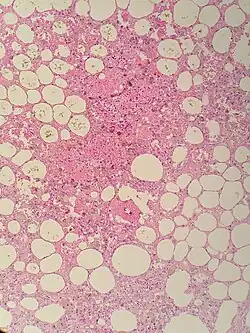

Sclerosing mesenteritis - note the hemosiderin, chronic inflammation

The disorder is identified by histopathology showing fat necrosis, fibrosis and chronic inflammation of the small intestine. Examination of the mesentery may indicate a solitary mass, but diffuse mesentery thickening is common.[4][6]